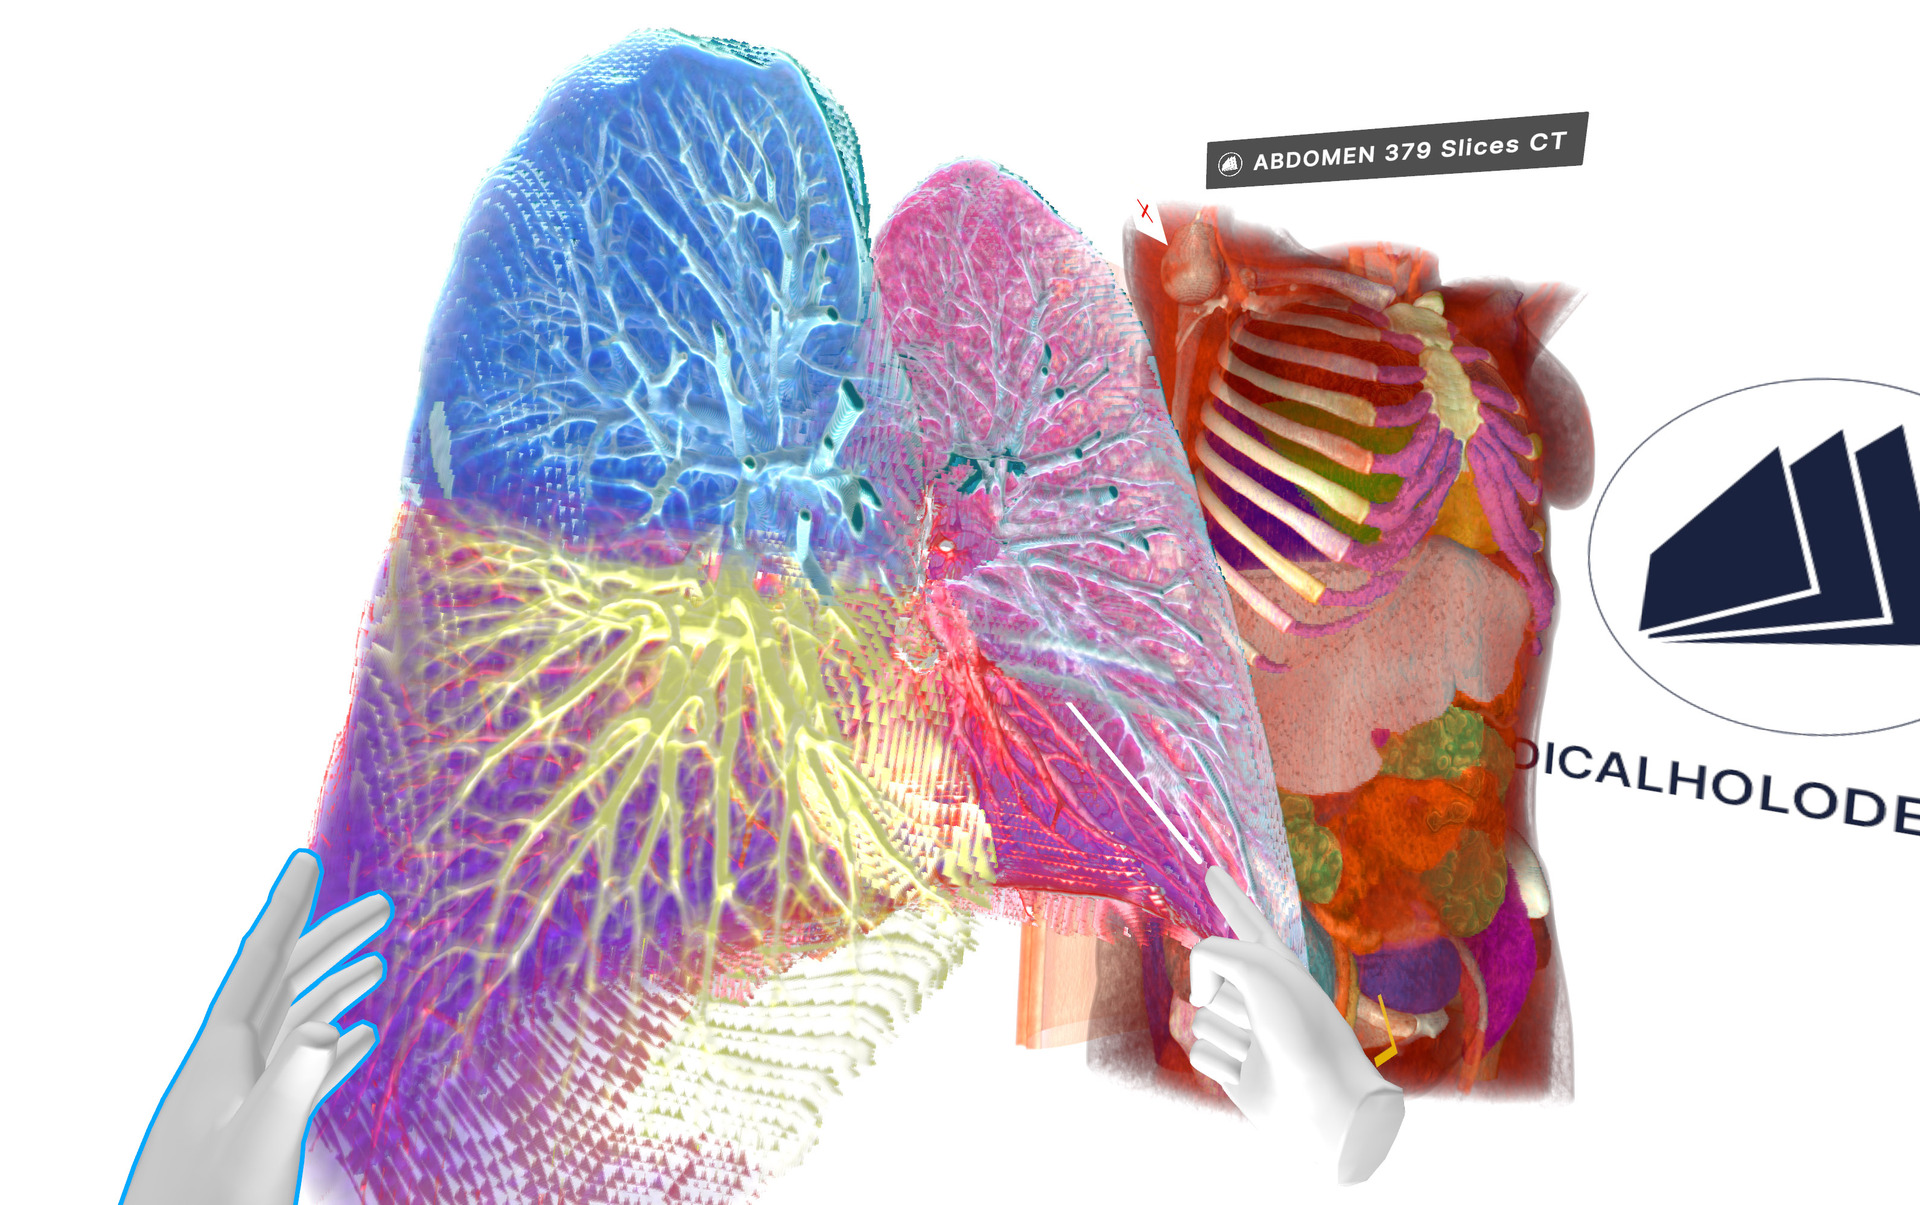

Medicalholodeck’s latest update to version 1.3.1 delivers new AI-powered segmentation for liver vessels and oculomotor muscles, optimized volumetric rendering for big datasets with high performance, and language support for Brazilian Portuguese.

Read moreSummer update boosts medical imaging and anatomy education with Anatomy Master 2, a 3D atlas for VR/AR, extended cloud segmentation with MONAI Model Zoo, advanced AI visualization tools, and improved workflows.

With this new function, medical professionals can now easily create 3D models of organs and bones in virtual reality and export the data for 3D printing. The whole process takes place inside VR, allowing unprecedented accuracy and speed.